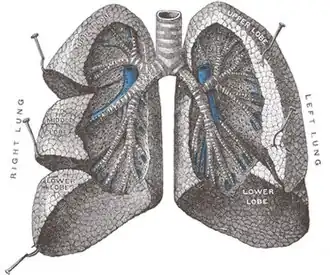

Vista frontal dos pulmões (cortados) | |

Os pulmões humanos são divididos em segmentos denominados lobs (pronuncia-se "lóbos", com a primeira vogal aberta). O pulmão esquerdo possui dois lobs e o direito possui três.[1]

O pulmão direito é mais espesso e mais largo que o pulmão esquerdo, e é também um pouco mais curto, pois o diafragma é mais alto no lado direito para acomodar o fígado.[4] O pulmão esquerdo tem uma concavidade que é a incisura cardíaca.[4]